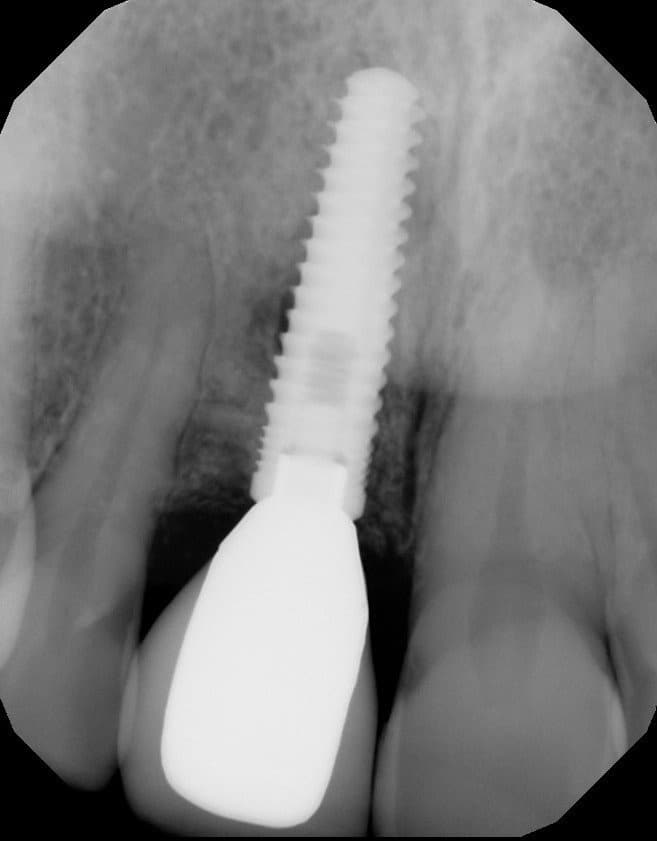

Figure 7 from Implant complications biomechanical and esthetic

This dental implant was placed too close to the adjacent tooth Dental Implants Too Close Together Implants placed too close to an adjacent tooth root are usually the result of poor treatment planning (eg, inadequate space), poor surgical technique (eg, improper angulation), or the placement of too wide of an implant body. Sometimes, a dental surgeon may inadvertently place a dental implant too close to a nerve. If the implant is not deep enough, the abutment. Dental Implants Too Close Together.

Figure 7 from Implant complications biomechanical and esthetic Dental Implants Too Close Together Implants placed too close to an adjacent tooth root are usually the result of poor treatment planning (inadequate space), poor surgical technique. Implants placed too close to an adjacent tooth root are usually the result of poor treatment planning (eg, inadequate space), poor surgical technique (eg, improper angulation), or the placement of too wide of an implant body. The upper. Dental Implants Too Close Together.